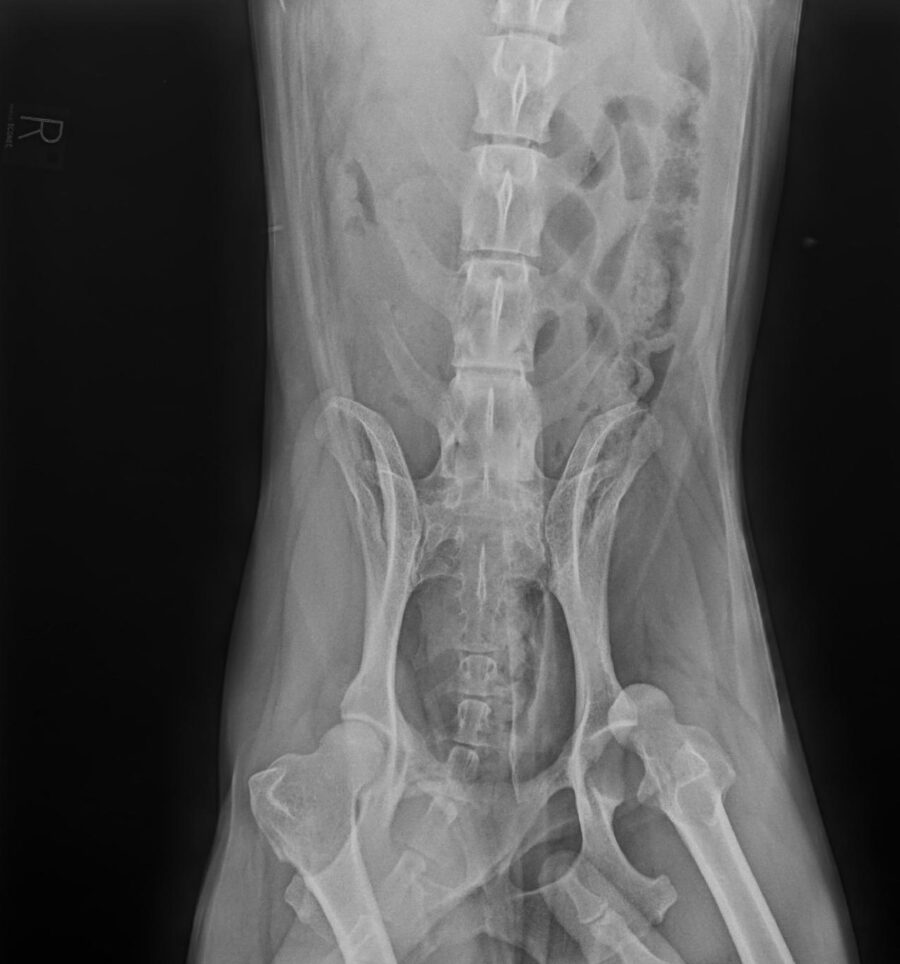

• Fracturen met platen, schroeven of pinnen

• Heupkopresectie